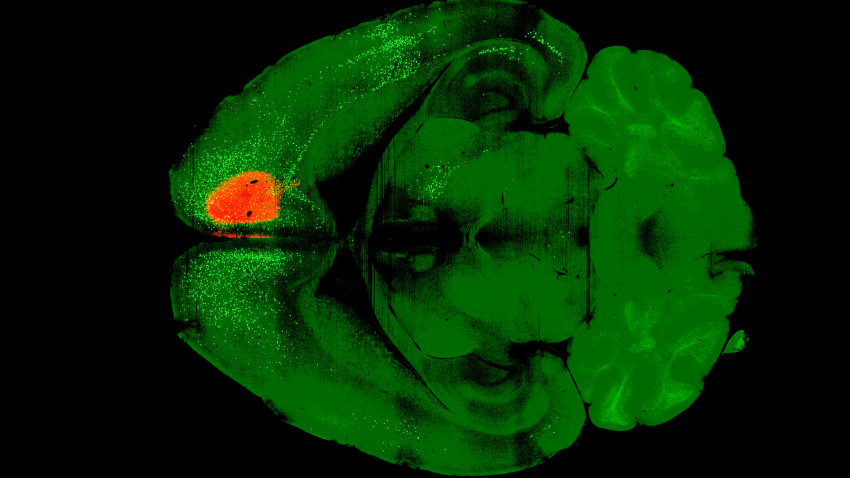

The experimental process involved injecting a single dose of psilocybin into the frontal cortical pyramidal neurons of mice. Following this, a variant of the rabies virus was introduced to label the connected neurons with fluorescent proteins. After a week, imaging revealed that psilocybin had weakened certain recurrent connections within the cortex, which may explain the tendency for individuals with depression to fixate on negative thoughts.

Unexpectedly, the study found that psilocybin’s effects were not limited to isolated brain regions but involved widespread changes across the entire brain. Kwan remarked, “This is really looking at brain-wide changes. That’s a scale that we have not worked at before.”